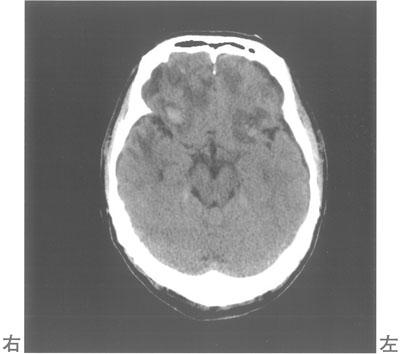

20

理学療法士実地問題 -

第55回 午後

重要度:重要

75歳の男性。脳挫傷。飲酒しトイレで倒れていた。頭部CTを示す。明らかな運動麻痺はなく、反復唾液嚥下テスト〈RSST〉は5回/30秒である。改訂水飲みテスト〈MWST〉や食物テストでは嚥下後の呼吸は良好でむせもない。義歯を使用すれば咀嚼可能であるが、実際の食事場面では自分で食物を口に運ぼうとしない。この患者の摂食嚥下で障害されているのはどれか。

1

先行期

2

準備期

3

口腔期

4

咽頭期

5

食道期